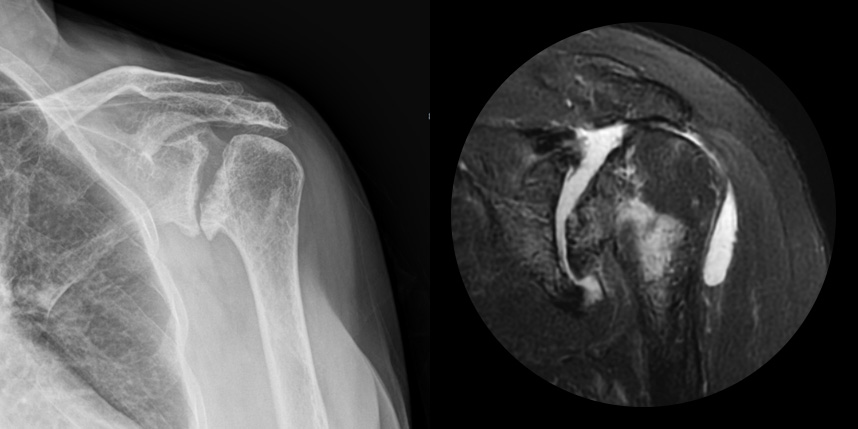

발생부위와 원인으로는 퇴생성, 골절이나 탈구 등 외상의 합병증, 류마티스, 진행된 회전근개파열, 골괴사 등에 의해 발생하게 됩니다.

주로 젊은 층에서는 외상, 류마티스 관절염, 수술 등에 의해 2차적으로, 50대 이후에는 퇴행성으로 생기게 됩니다.

어깨 퇴행성은 많이 써서 닳고 노화에 따른 변화가 생긴 것으로, 말 그대로 어깨가 많이 사용되면서 연골이 닳아서

마모돼어 생기는 관절염입니다. 어깨 회전근개 관절병증 원인으로는 어깨 힘줄 파열을 방치했을 때 관절이 틀어진 상태에서 계속

사용하게 되면 관절이 많이 상해서 관절염까지 진행되며, 이런 경우 회전근개파열의 결과로 생긴 관절병이라고 합니다.

최근에 퇴행성 관절염, 류마티스 관절염 이외에도 많은 환자가 발생하고 있습니다.